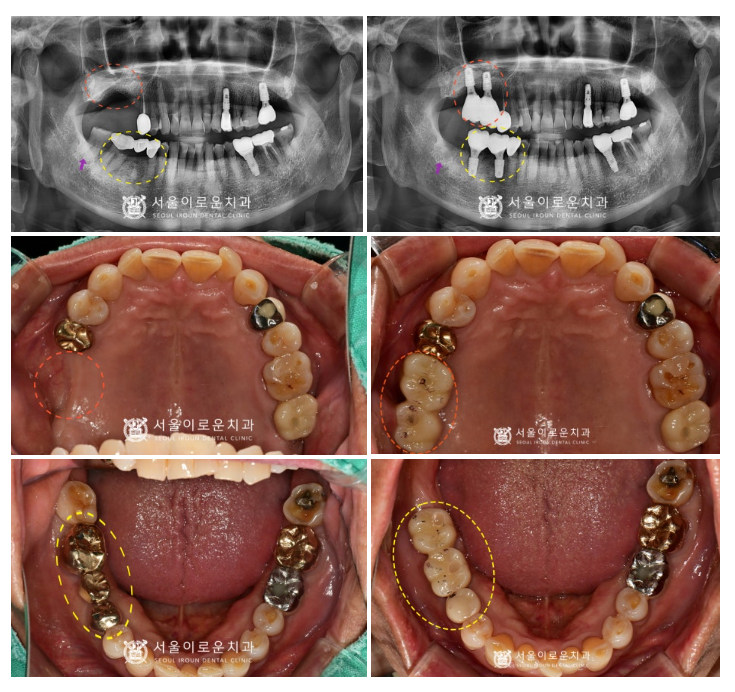

술 후 파노라마와 3D-CT를 통해

발치 후 즉시 임플란트와

상악동 거상술을 동반한 임플란트가

안정적으로 식립된 것을 체크하였답니다.

임플란트 / 크라운 수복 / 사랑발치를

모두 마무리 한 모습입니다.